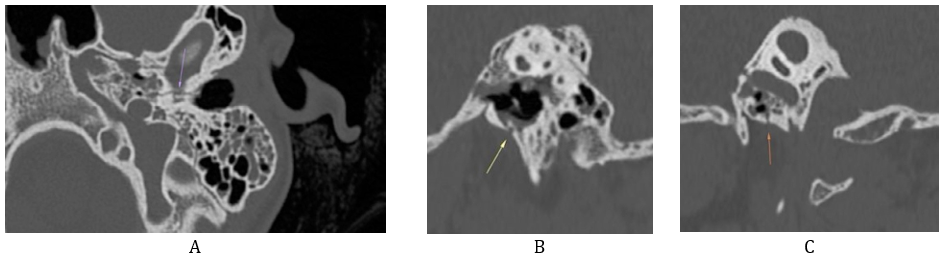

Clinical examination showed a left peripheral facial nerve palsy graded IV on the House–Brackmann (HB) scale, associated with otorrhagia and conductive hearing loss. Temporal bone CT demonstrated a horizontal fracture line passing through the anterior wall of the tympanic bone, sparing the carotid canal, and associated with partial hemotympanum and mastoid opacification. Pure-tone audiometry confirmed a moderate conductive hearing loss on the left side. Electroneuromyography revealed severe axonal injury without evidence of neurotmesis.

A course of oral corticosteroids (prednisone 1 mg/kg/day for one month, with gradual tapering) was initiated. Clinical improvement was noted within one week, with complete resolution of both facial dysfunction and hearing deficit after one month of follow-up.

Figure 9: Axial (A) and sagittal (B, C) CT images of the temporal bone showing a transverse fracture of the petrous portion sparing the otic capsule